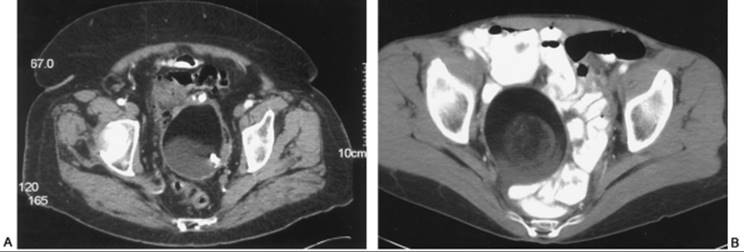

In the event that ultrasonographic findings are uncertain or more information is needed before surgical evaluation is undertaken, CT can be helpful. The conventional CT scan obtains images one slice at a time. Slice thickness is usually 8 to 10 millimeters, and patient immobilization is critical for obtaining clear views. Each slice is then reconstructed by the computer to result in a full image of the pelvis. Usually radiopaque oral agents are used to opacify the gastrointestinal tract. Intravenous contrast can be administered to visualize vascular and genitourinary structures. Ovarian nodularity, septations, and fat can be characterized well by CT scan. Additionally, if there is a concern that ultrasonographic findings may be reflecting a loop of bowel, CT can clarify this by using contrast. CT scans are fairly accurate for diagnosing a dermoid cyst given the combination of fat and calcification in these neoplasms (Fig. 56.5). If there is some concern that an adnexal mass may be uterine, such as in the case of myomas, CT can clarify this. Lastly, if an abdominal and pelvic CT scan is ordered, information regarding the rest of the lower abdomen and upper abdomen can be obtained.

FIG. 56.5. Computed tomography image of dermoid cysts. A: Internal calcification.